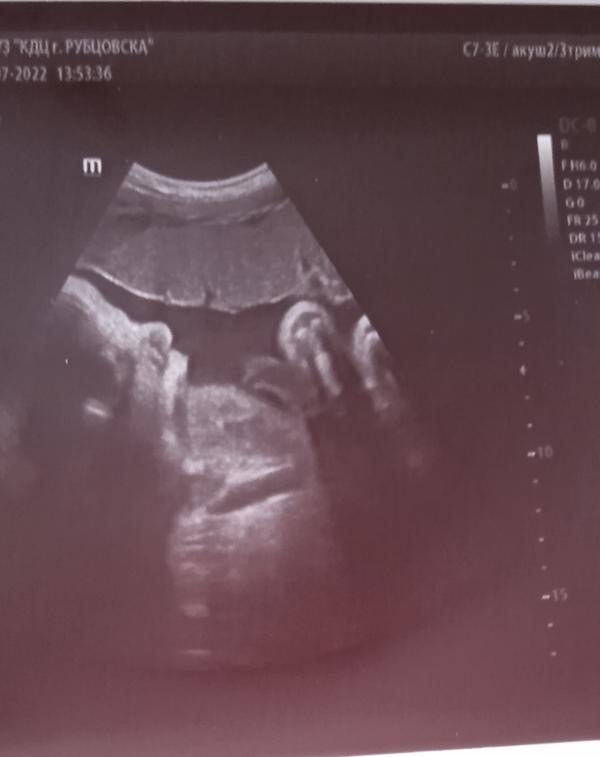

100 день беременности: УЗИ показало вес 1900г, все хорошо! Ждем Мишутку!

Сегодня была на 3 узи у нас 100% 👦. Мы уже весим 1900гг. По узи всё хорошо. Ждëм нашего Мишиньку 😍